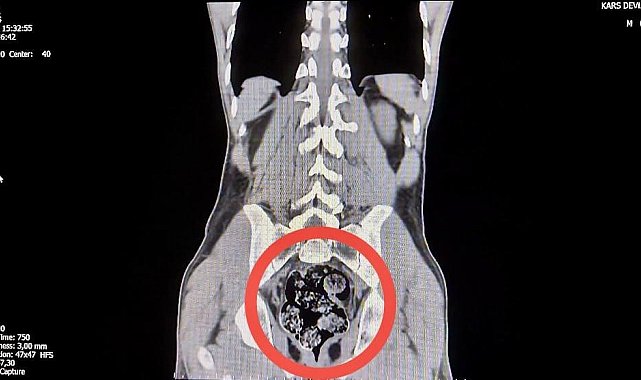

İl Emniyet Müdürlüğü'ne getirilen ve durumundan şüphelenilen kuryelerden Shekarbaghanı, detaylı arama için Kars Harakani Devlet Hastanesi'ne götürüldü. Hastanede yapılan emar ve röntgen kontrollerinde şüphelinin makatında cisim olduğu belirlendi. Yapılan cerrahi müdahalede, şüphelinin makatından 7 parça halinde 203,02 gram metamfetamin çıkarıldı.